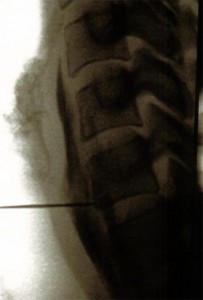

Posición del paciente en decúbito supino con almohada bajo los hombros, se coloca el arco de fluoroscopia en posición para visualizar C6-C7-T1 y se marca el punto de entrada en la piel haciéndolo coincidir en la unión de la apófisis transversa con el cuerpo vertebral de C7, previa separación con el dedo índice de la mano, de la tráquea y el pulso carotideo. Se le pide al paciente que respire por la boca y se introduce la aguja un poco medial y craneal para evitar el vértice pulmonar y la arteria vertebral. Una vez haga contacto óseo se retira la aguja 2mm  y pasamos el arco de fluoroscopia posición lateral y se debe ver la profundidad de la aguja ventral a una línea imaginaria que pasa ventral a los forámenes intervertebrales. Inyectar 0.5ml de contraste para asegurarnos la posición correcta.